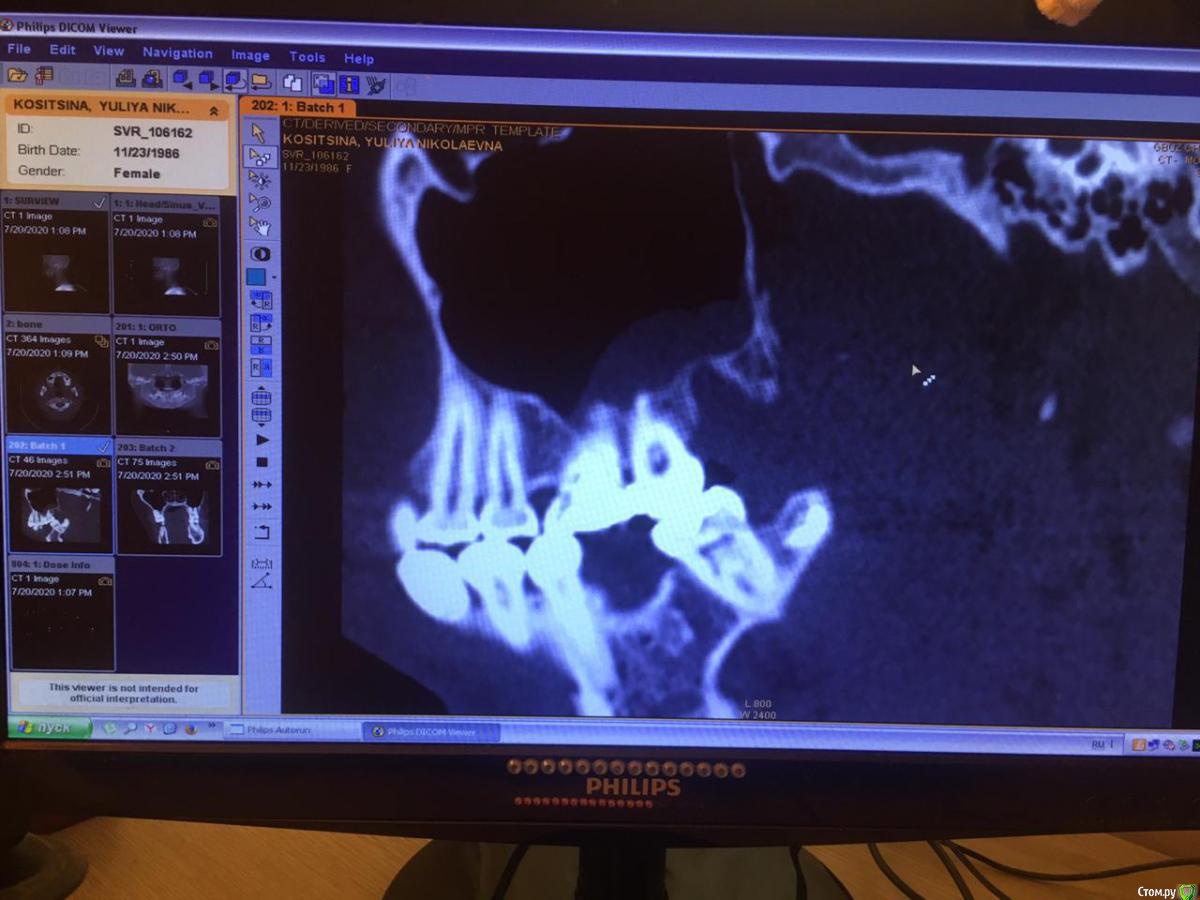

Юлия2386 Опубликовано 30 июля, 2020 Поделиться Опубликовано 30 июля, 2020 Добрый день, уважаемые врачи! Прошу вашей помощи, так как уже замучалась я конкретно. У меня уже 9 месяцев боли в правой стороне лица давящего характера. Давит на лоб, глаз, иногда висок. С декабря 2019 выявили фронтит-гайморит, проходила лечение у Лора и ещё невролога. Окончательного результата по выздоровлению за это время не достигнуто. Видимо это одномерный гайморит, так как постоянно какое-то воспаление формировалось у зубов 1.6;1.7;1.8. Многие стоматологи не видят проблем в зубе 1.6. Посоветовали удалить зуб 1.8 так как там был глубокий десневого карман. Удалила, а воспаление разрослось ещё больше (после удаления поцарапала щеку зубом 1.7, возможно из-за этого разрослось воспаление?!) После удаления прошёл месяц, а картина сейчас такая https://yadi.sk/d/ziceEN_jVZ9IkwВ итоге последний врач сказал, что все-таки проблема идёт от зуба 1.6, так как не запломбирован один канал, но из-за того что у зуба входят корни в гайморовых пазуху, лечить его не видет смысла, порекомендовал его удалить и через лунку вычиститься всю слизь, но он этим не занимается. Теперь я замешательстве и не знаю, что мне с этим делать, а самое ужасное, что глаз от этого болит( Уважаемые доктора, очень прошу вашей помощи, выскажите пожалуйста ваше мнение и может посоветуете к кому с этим можно обратиться в Москве. Ссылка на комментарий

wladdX Опубликовано 31 июля, 2020 Поделиться Опубликовано 31 июля, 2020 Представленная спиральная КТ не позволяет детально рассмотреть корневые каналы зубов и тп, чтобы получить какое-то внятное суждение.На уровне зубов 18, 17 и 16 есть локальное утолщение слизистой оболочки синуса и это всё, что из этого исследования можно выяснить. Адекватность обтурации корневых каналов зуба 16 оценить не представляется возможным (по крайней мере в моём понимании).Я бы порекомендовал сделать КЛКТ (конусно-лучевую компьютерную томографию), используемую в стоматологии. Ссылка на комментарий